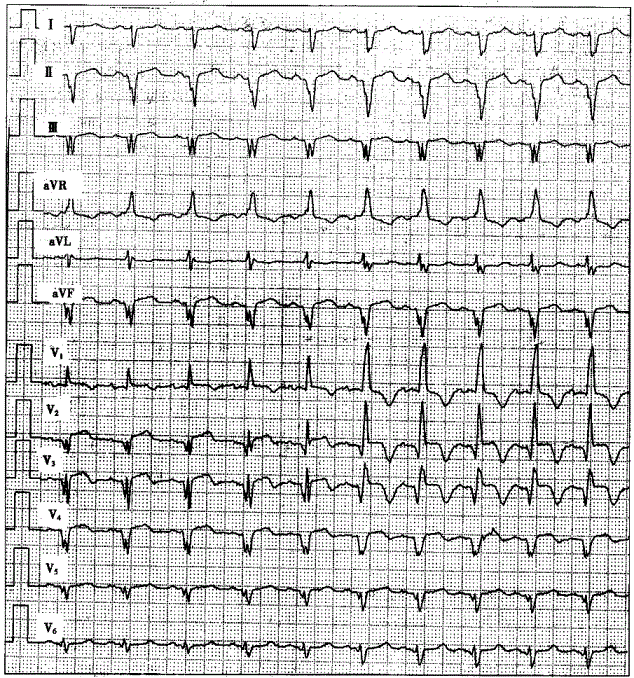

问题 患者女性,61岁,冠心病。因突发胸痛2小时就诊,心电图如下图所示,应诊断为

选项 A.急性下壁心肌梗死 B.急性下壁、广泛前壁心肌梗死,合并左束支阻滞 C.急性下壁、广泛前壁心肌梗死,合并右束支阻滞 D.急性广泛前壁心肌梗死,非阵发性室性心动过速 E.急性广泛前壁心肌梗死

答案 C

解析 :窦性P波规律出现,Ⅱ、Ⅲ、aVF、V~V导联出现病理性Q波,ST段呈弓背向上抬高。QRS波群时间由正常逐渐增宽,但起始部分Q波未变,仅后半部分逐渐增宽;V导联QRS波群呈qR型,V~V导联QRS波群由QS型转变为QR型。应诊断为急性下壁、广泛前壁心肌梗死,合并右束支阻滞(由不完全右束支阻滞演变到完全性右束支阻滞)。